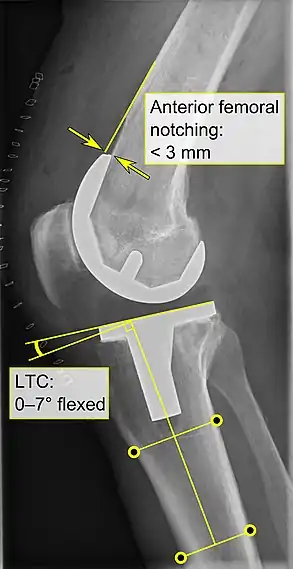

Knee replacement is routinely evaluated by X-ray, including the following measures:

- Anterior femoral notching (the femoral component causing reduced thickness of the distal femur anteriorly), seems to cause an increased risk of fractures when exceeding about 3 mm.[63]

- LTC: lateral (or sagittal) tibial component angle, which is ideally positioned so that the tibia is 0–7° flexed compared to at a right angle with the tibial plate.[62]